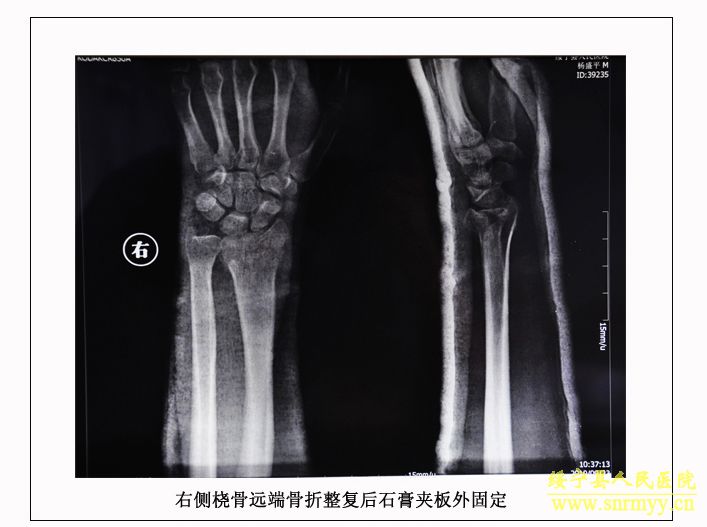

经检查:当时病人体温36.5℃、脉搏105次/分钟、呼吸25次/分钟、血压152/98mmhg,呈昏迷状,头面部、右手、左下肢均不同程度受伤,双侧瞳孔不等大,光反射消失;同时右手臂和左大腿均有骨折。GCS评分:仅4分,根据评分标准(轻度颅脑损伤为12—15分、中度为8—12分、重度为5—8分、极重度为3—5分)该病人属于极重度颅脑损伤。CT检查结果为脑干挫裂伤、双侧额叶、左颞叶、右顶叶脑挫裂伤、左侧颞部硬膜外、下血肿,左顶硬膜下血肿,蛛网膜下腔出血,脑室内积血,左侧额部下积液,左眼框内侧壁,枕骨骨折。X光片显示右桡骨粉碎性骨折,左股骨干骨折。诊断为:1、极重度颅脑损伤:(1)脑干挫裂伤。(2)双侧额叶、左颞叶、右顶叶脑挫裂伤。(3)右颞部硬膜外血肿。(4)外伤性蛛网膜下腔出血。(5)枕骨骨折。(6)头皮多处挫裂伤。2、右桡骨粉碎性骨折。3、左股骨干骨折。临床上如此严重的脑损伤死亡率极高,再加上合并多处骨折创伤,病人危在旦夕。

经再次检查,病人的身体状况明显好转,但意识模糊。9月28日,病人意识逐渐清楚。为方便护理,让病人早日康复,由沈建辉副院长亲自主刀,刘兴淼医师为助手,为病人实施了左股骨开放复位和交锁髓钉内固定术。10月21日,病人生活基本能自理,近日即可出院。 (2010.10.26)